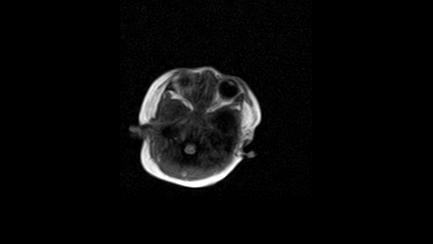

标题: PED3413:患儿女6天体检

缺血缺氧性脑病

6天为新生儿,髓鞘发育正常;左侧颞顶叶蛛网膜下腔增宽,请结合临床。

1。缺血缺氧性脑病2。左侧颞顶叶外部性脑积水,可观察

半卵圆中心上方层上可见对和乐大脑皮质t1高信号,考虑有hie可能,不知有何症状,建议加做dwi及复查

符合缺氧缺血性脑病影像表现。